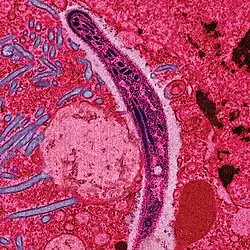

Malaria in humans develops via two phases: an exoerythrocytic (hepatic) and an erythrocytic phase. When an infected mosquito pierces a person's skin to take a blood meal, sporozoites in the mosquito's saliva enter the bloodstream and migrate to the liver. Within 30 minutes of being introduced into the human host, they infect hepatocytes, multiplying asexually and asymptomatically for a period of 6–15 days. During this so-called dormant time in the liver, the sporozoites are often referred to as hypnozoites.[6] Once in the liver, these organisms differentiate to yield thousands of merozoites which, following rupture of their host cells, escape into the blood and infect red blood cells, thus beginning the erythrocytic stage of the life cycle.[7] The parasite escapes from the liver undetected by wrapping itself in the cell membrane of the infected host liver cell.[8]

Within the red blood cells the parasites multiply further, again asexually, periodically breaking out of their hosts to invade fresh red blood cells. Several such amplification cycles occur. Thus, classical descriptions of waves of fever arise from simultaneous waves of merozoites escaping and infecting red blood cells.